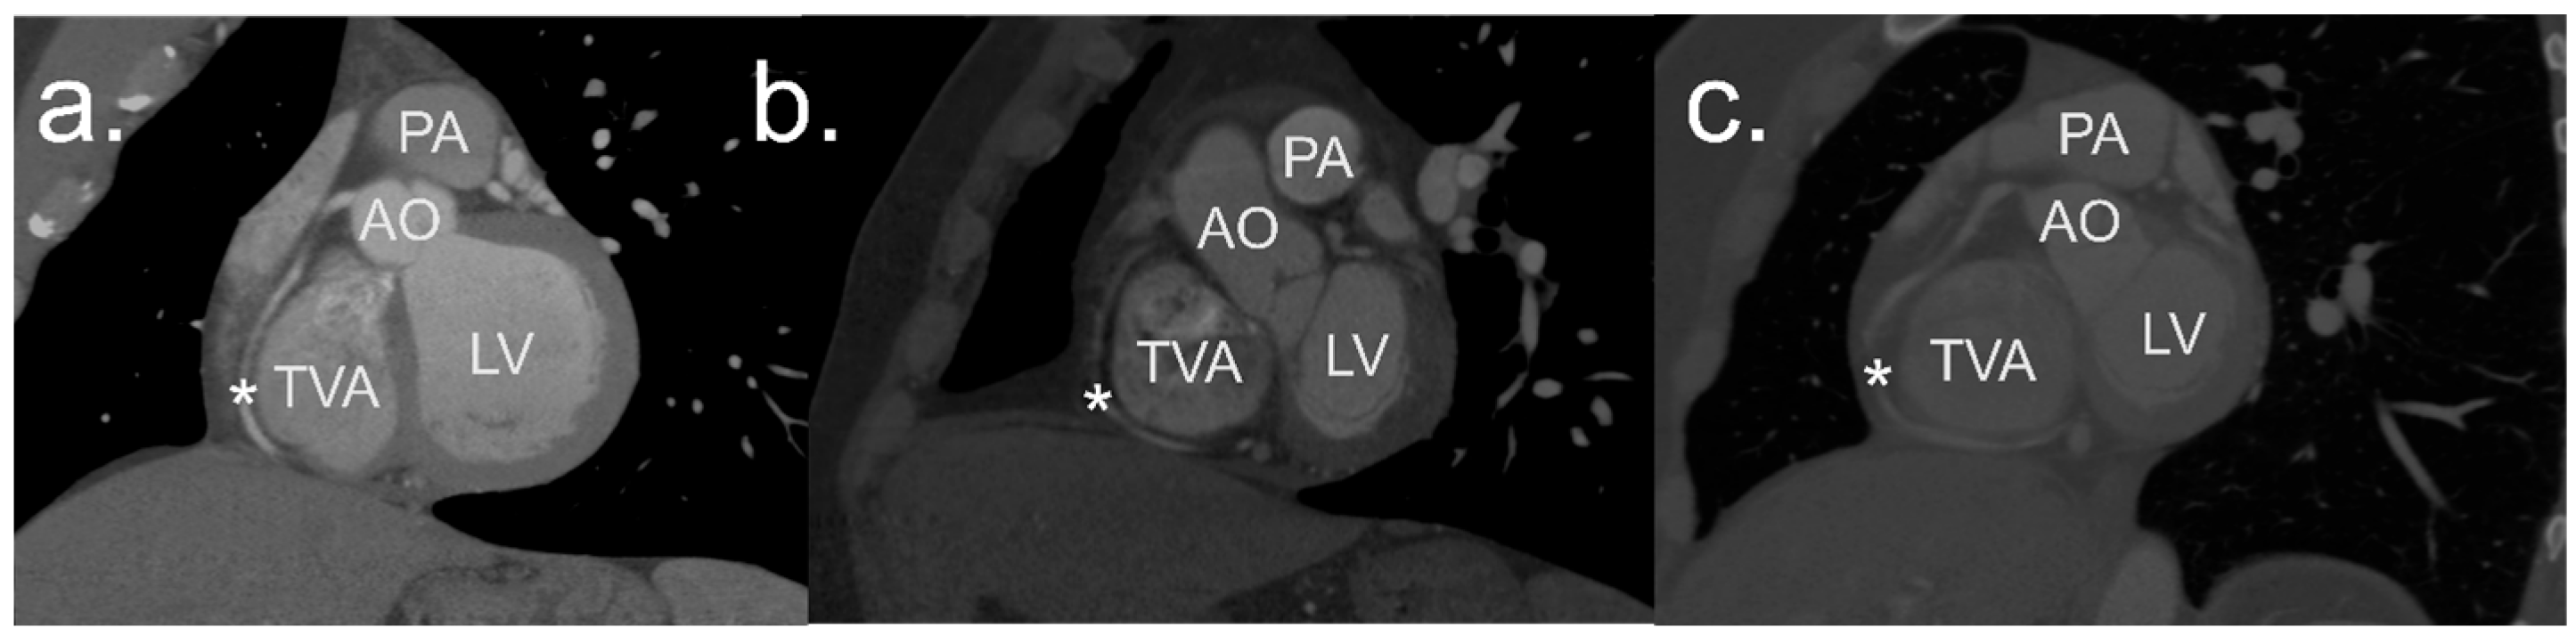

2.2. Image Processing and Analysis

2.3. Definitions

2.4. Measurements